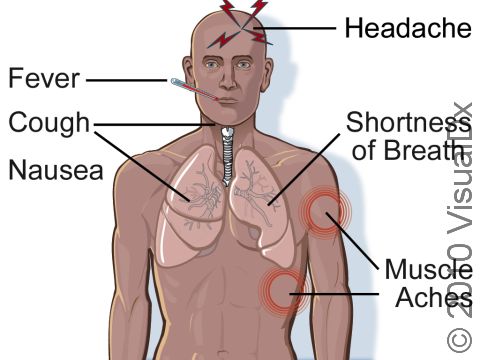

Signs and symptoms of legionellosis usually develop within 14 days of exposure to the bacterium. The symptoms are not very different from many other illnesses, so legionellosis can be difficult to diagnose. The symptoms usually last for less than a week and get better within 5 days.

Symptoms of legionellosis include:

- Fever

- Chills

- Cough, sometimes with blood

- Feeling generally weak and achy (malaise)

- Headache